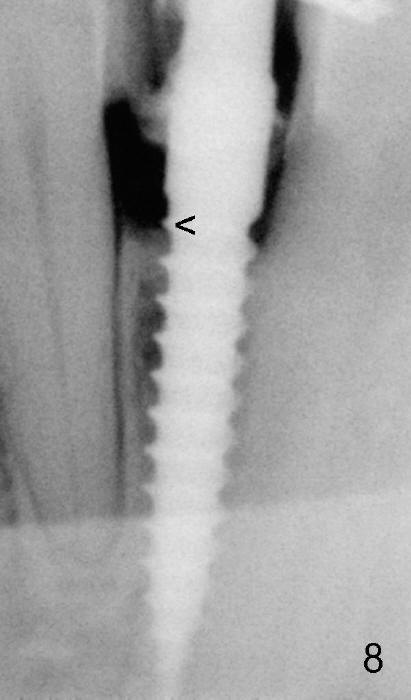

Fig.8: 2 years 2 months postop, still not permanently restored. The 1st thread is now supracrestal. The implant crown remains normal 1 year 10 months post 2nd cementation (4 years 10 months postop, Fig.13).

Return to Immediate Loading Fig.8 Last Next 1-Piece 2 mm